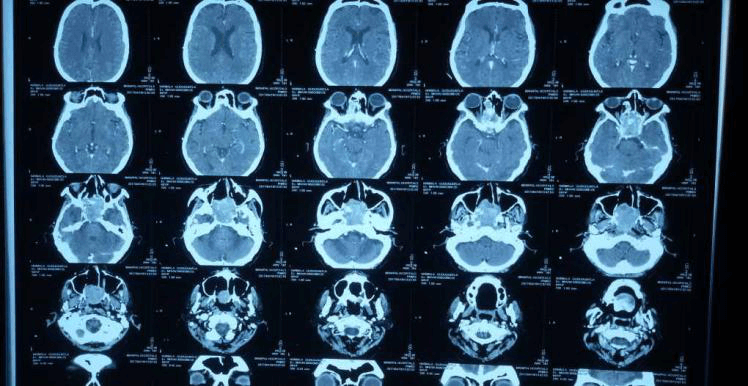

2012 সালের অক্টোবরে তিনি আমাদের কাছে ফিরে এসেছিলেন, ধীরে ধীরে প্রগতিশীল ডান-পার্শ্বযুক্ত নাক ব্লক, ফুসফুস অনুনাসিক স্রাব এবং মাঝে মাঝে 2-বছরের মাথাব্যথার অভিযোগ করেছিলেন। এপিস্ট্যাক্সিস বা অন্যান্য ইএনটি অভিযোগের কোন ইতিহাস ছিল না। পরীক্ষায়, নাকের ডান দিকে মসৃণ পৃষ্ঠ ভরাট করে একটি বড় ভর ছিল, স্পর্শে রক্তপাত হয়নি। এবং একটি স্থূল DNS বাম. মস্তিষ্কের এমআরআইতে দেখা গেছে যে একটি মিশ্র তীব্র ক্ষত মাথার খুলির স্ফেনয়েড, ইথময়েড সাইনাস এবং সেলা এবং ক্লিভাসের অংশে অনুপ্রবেশ করে। সমস্ত রুটিন রক্ত এবং প্রস্রাব তদন্ত স্বাভাবিক ছিল. ক্ষতের বায়োপসি ইনভার্টেড প্যাপিলোমার পুনরাবৃত্তির পরামর্শ দিয়েছে। তিনি টিউমারের এন্ডোস্কোপিক ডিবুলিং করান। HPE এই সময় hemangiopericytoma পরামর্শ ছিল.

তিনি প্রথমে যশোদা হাসপাতালে ওপি হিসাবে এবং পরে স্থানীয় ইএনটি-এর সাথে অনুসরণ করেছিলেন। দুই বছর পর তার আমাদের সফরের সময় পুনরাবৃত্তির কোনো প্রমাণ পাওয়া যায়নি। এখন তিনি এপ্রিল মাসে আমাদের কাছে উপস্থাপন করেছিলেন যে এক সপ্তাহের জন্য ডান দিকের নাক দিয়ে রক্তপাত হচ্ছে। DNE ডানদিকে একটি অনিয়মিত মসৃণ পৃষ্ঠ ভাস্কুলার ভর দেখিয়েছে। CT PNS অনুনাসিক গহ্বরের পিছনের অংশে নরম টিস্যু ভর দেখায় যা ছাদ পর্যন্ত প্রসারিত হয় (ক্রিব্রিফর্ম প্লেট) এবং উপরে স্ফেনয়েড সাইনাস এবং নীচে নাসোফ্যারিনক্স পূরণ করে। তাকে রেডিওথেরাপি বিভাগে রেফার করা হয়েছিল যেখানে তাকে মস্তিষ্ক এবং কক্ষপথের নৈকট্যের কারণে IMRT-এর পরামর্শ দেওয়া হয়েছিল।